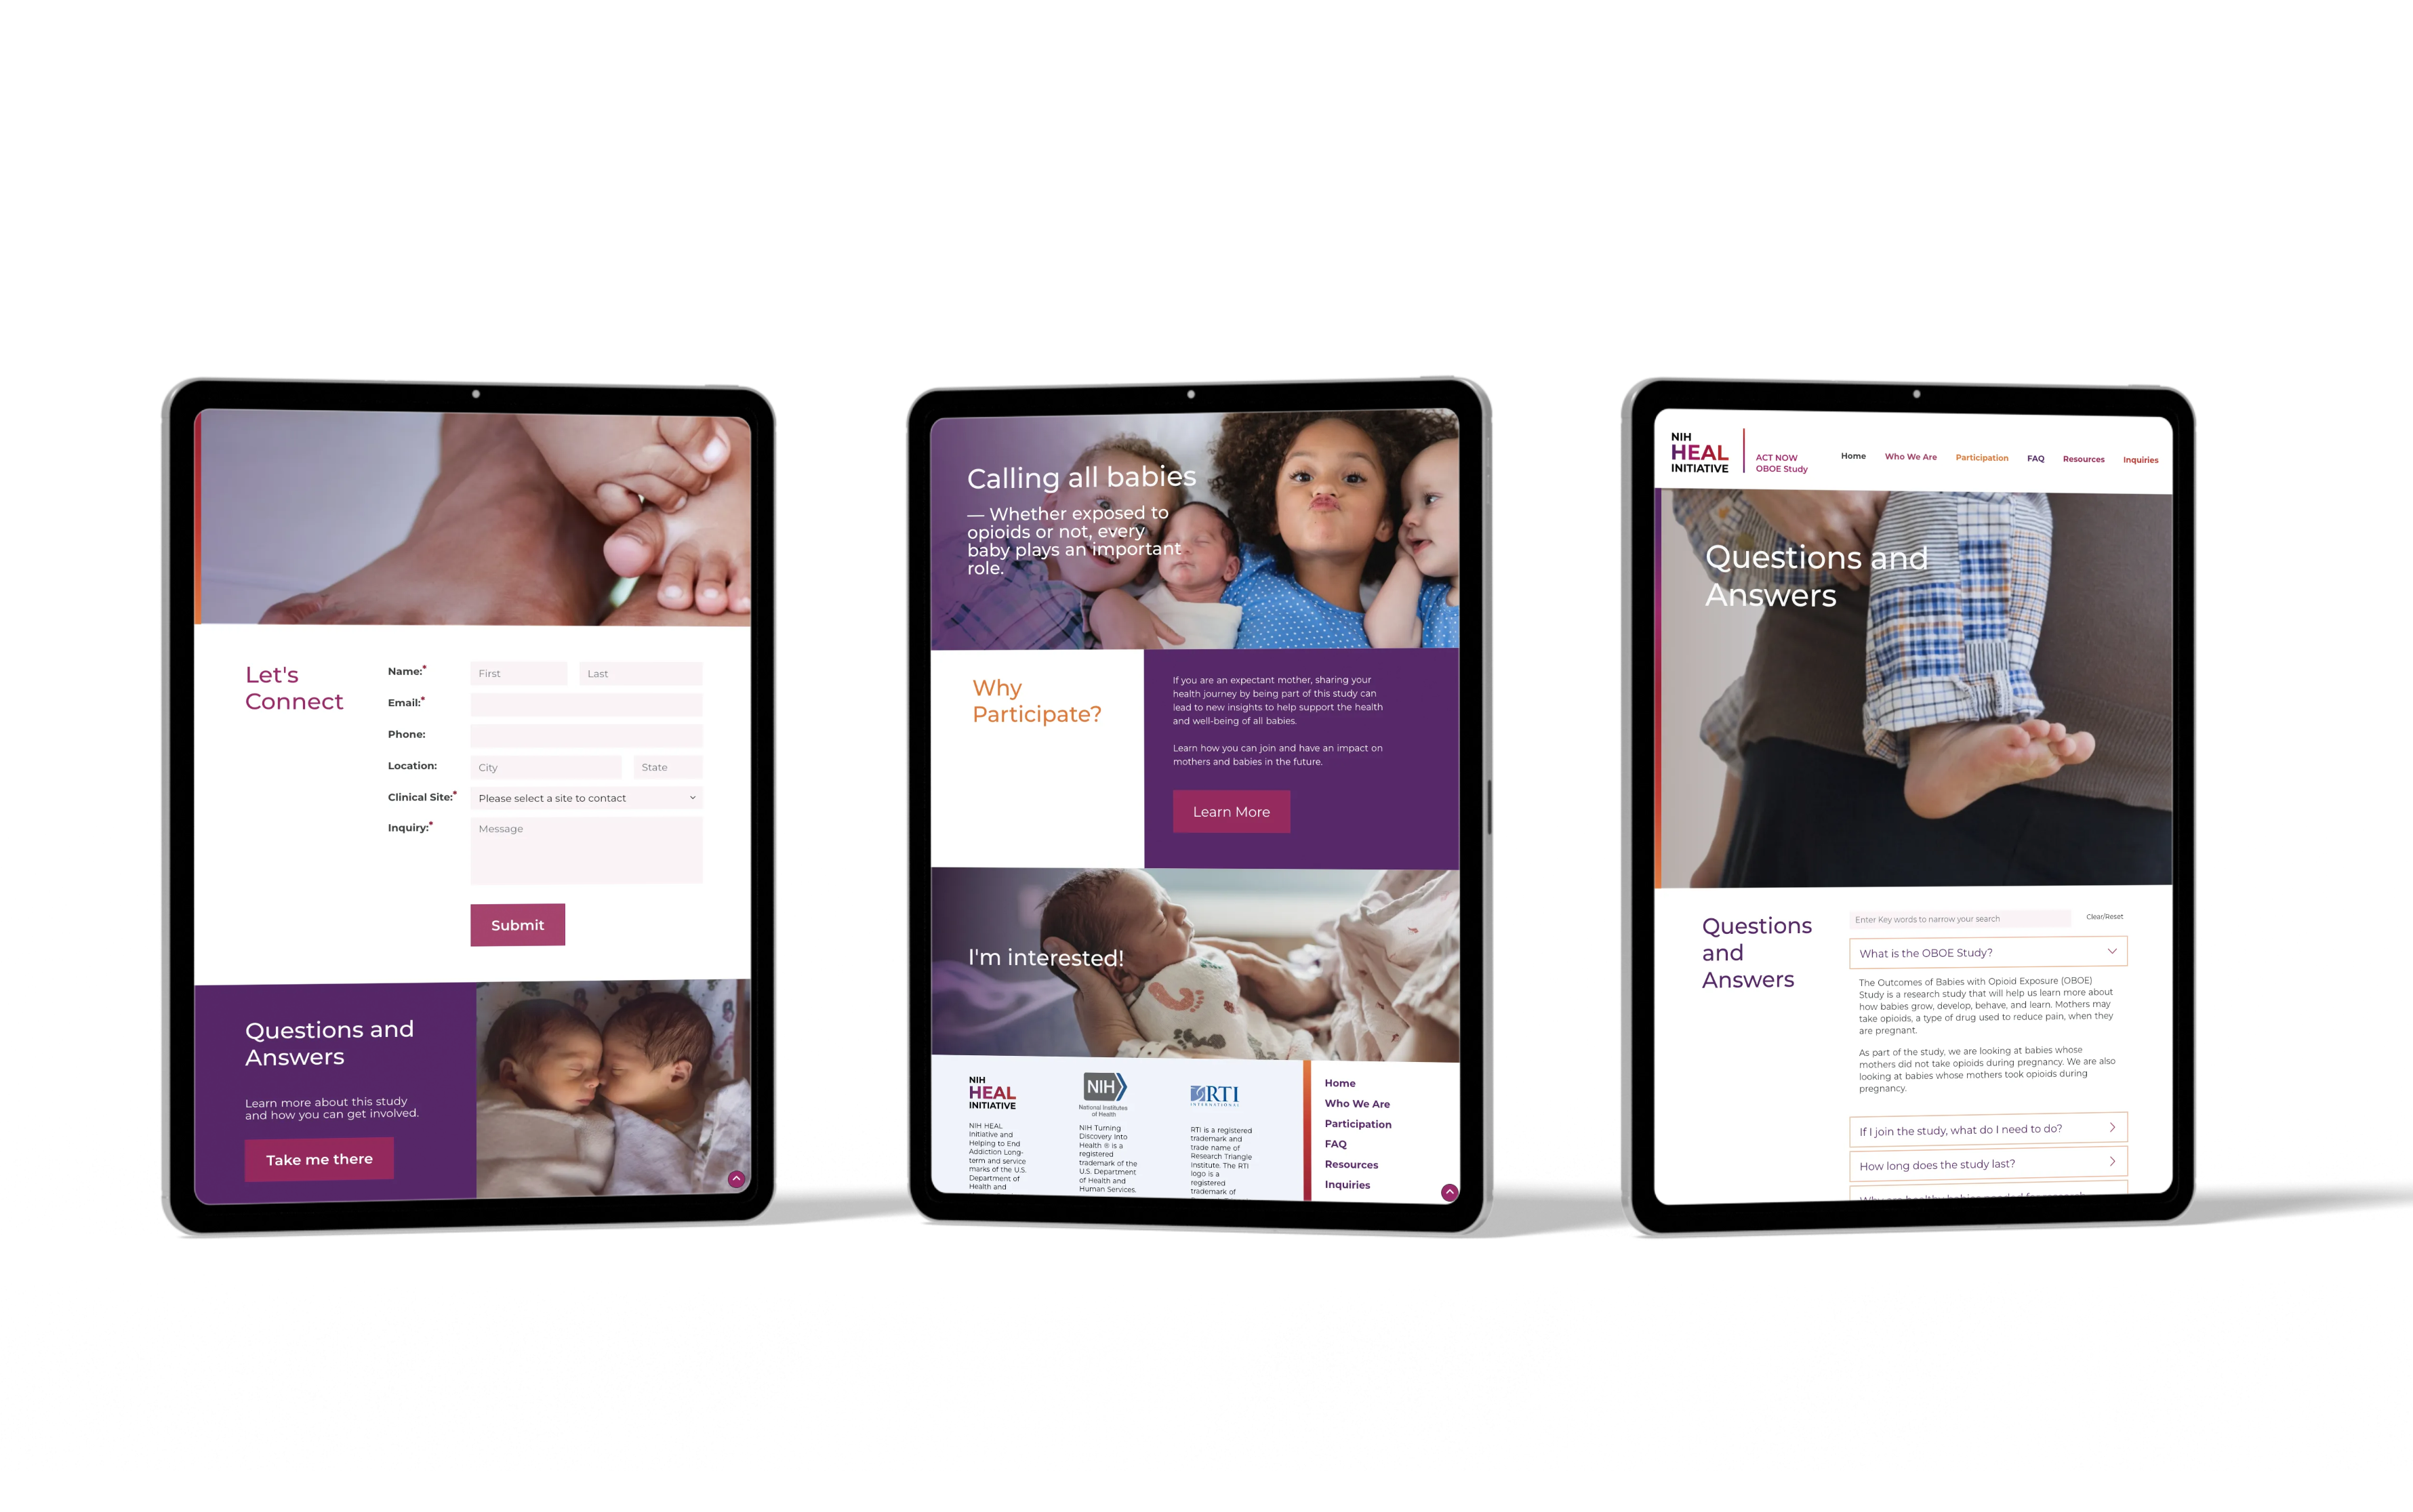

"There is a reason why the Catapult [RTI Merge] team continues to request Renee for assistance, she is the most talented UI/UX we have worked with at RTI."

"Renee exceeded all our expectations as usual. The branding she produced for our redesign has completely modernized our UI and has impressed all of our shareholders."